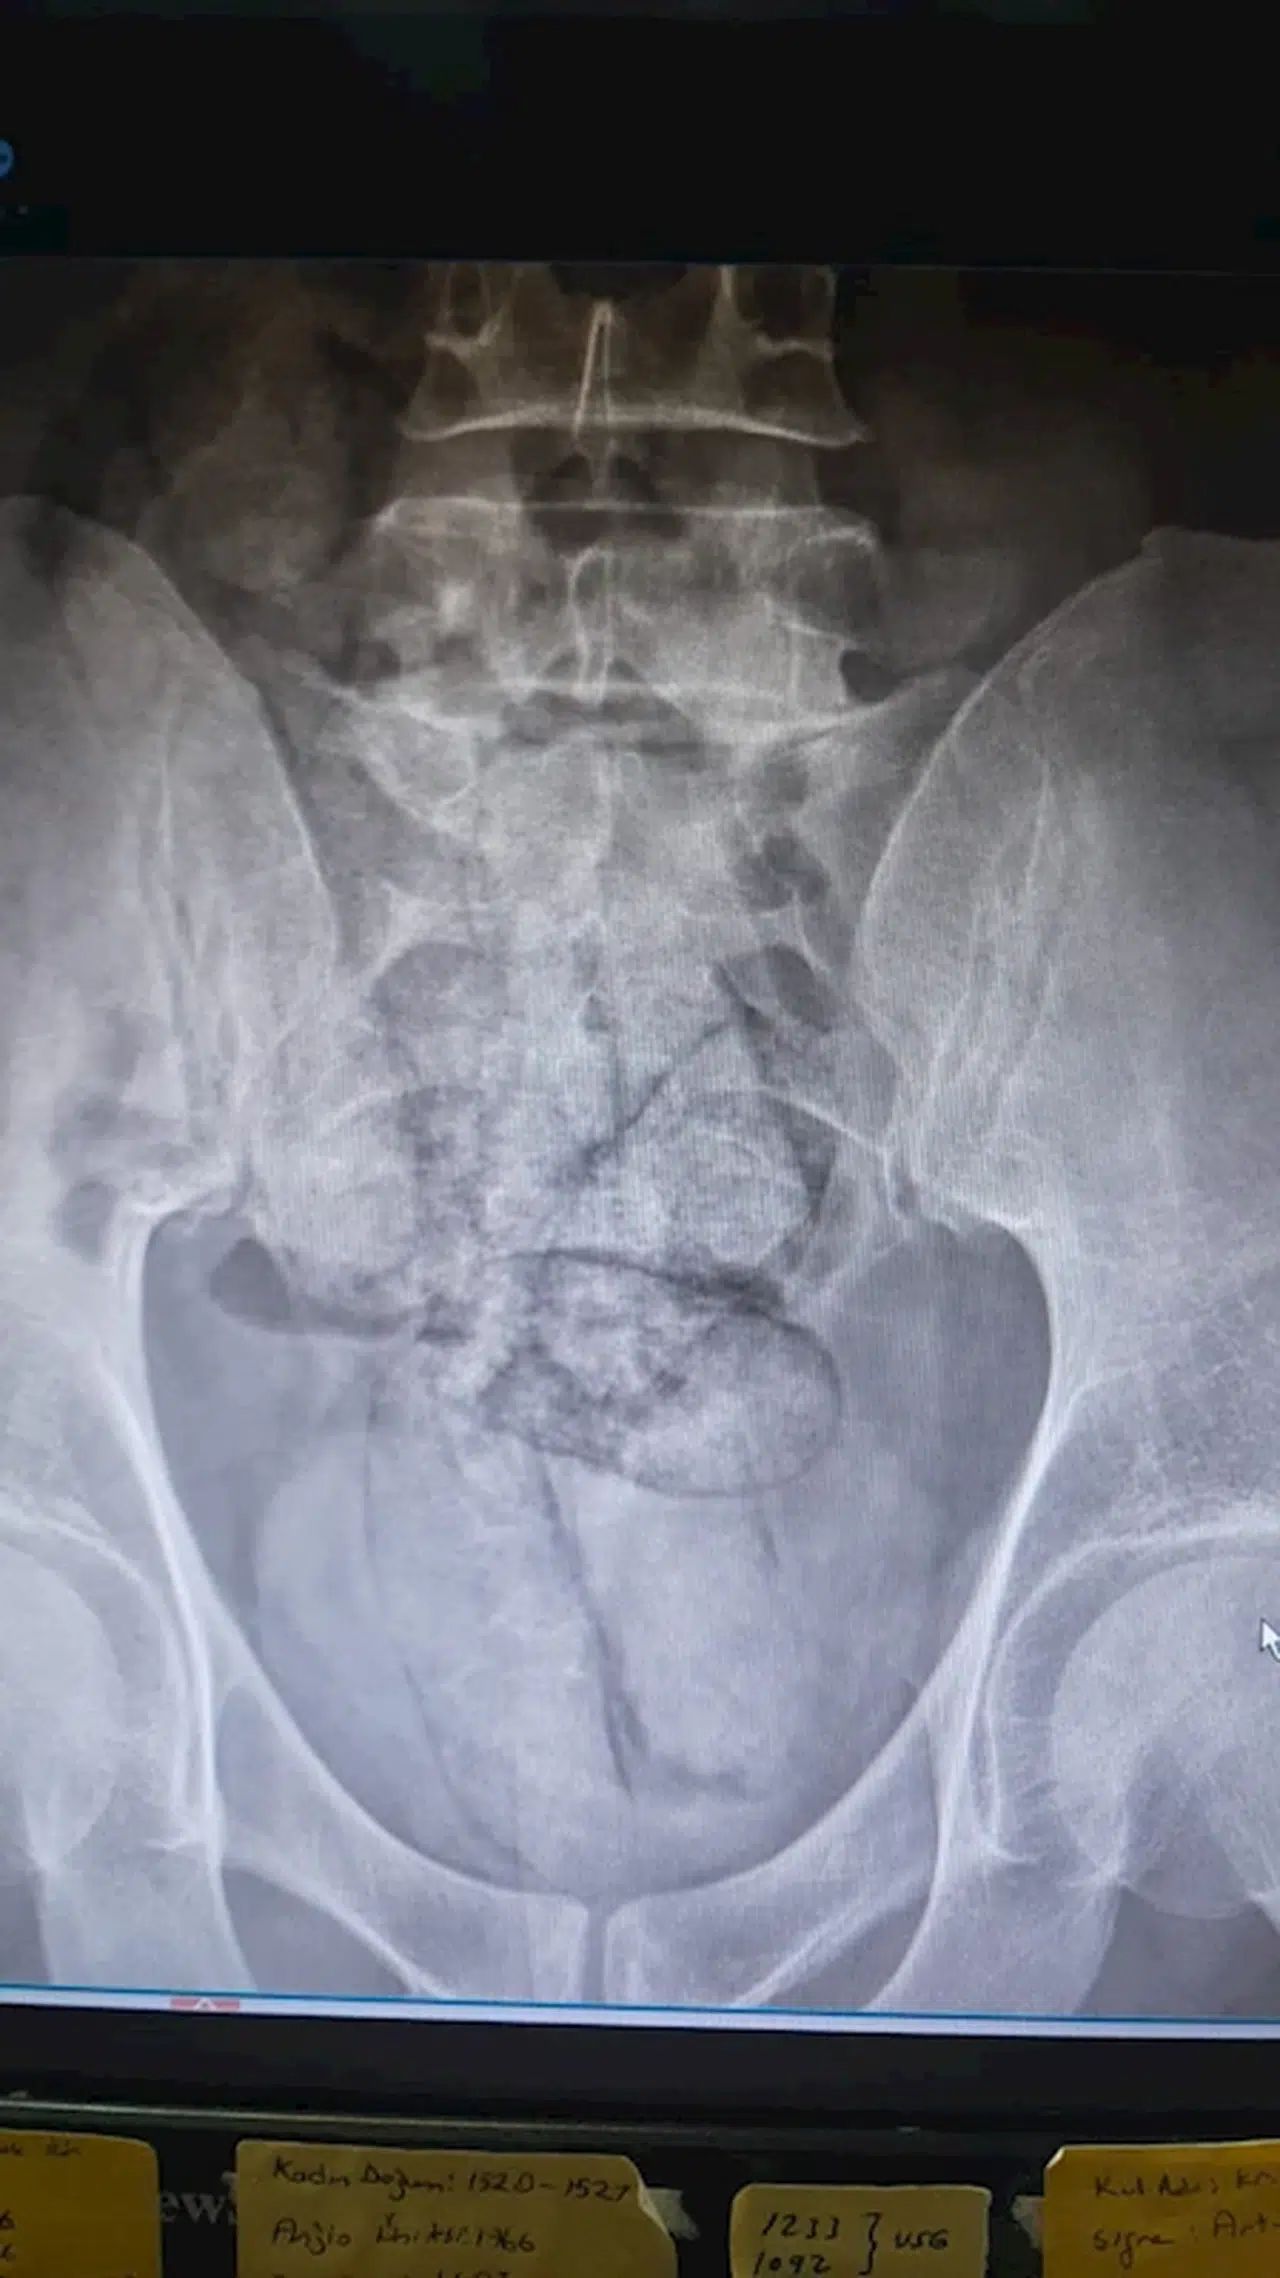

ARTVİN, (DHA)- ARTVİN’de bağırsağından 350 gram metamfetamin çıkan İran uyruklu F.R. (43) gözaltına alındı.

İl jandarma ekipleri, takip ettikleri İran uyruklu şüpheliyi dün saat 02.00 sıralarında Çayağzı Mahallesi’nde durdurdu. Üzerinde yapılan aramada herhangi bir olumsuzluğa rastlanmayan F.R., detaylı kontrol için hastaneye götürüldü. Artvin Devlet Hastanesi’nde tomografisi çekilen şüphelinin bağırsaklarında 10 paket halinde uyuşturucu madde taşıdığı belirlendi. Şüphelinin hayati tehlike oluşturabilecek şekilde sakladığı paketler, cerrahi müdahaleyle çıkarıldı. İncelemede paketlerin içinde toplam 350 gram metamfetamin olduğu tespit edildi.